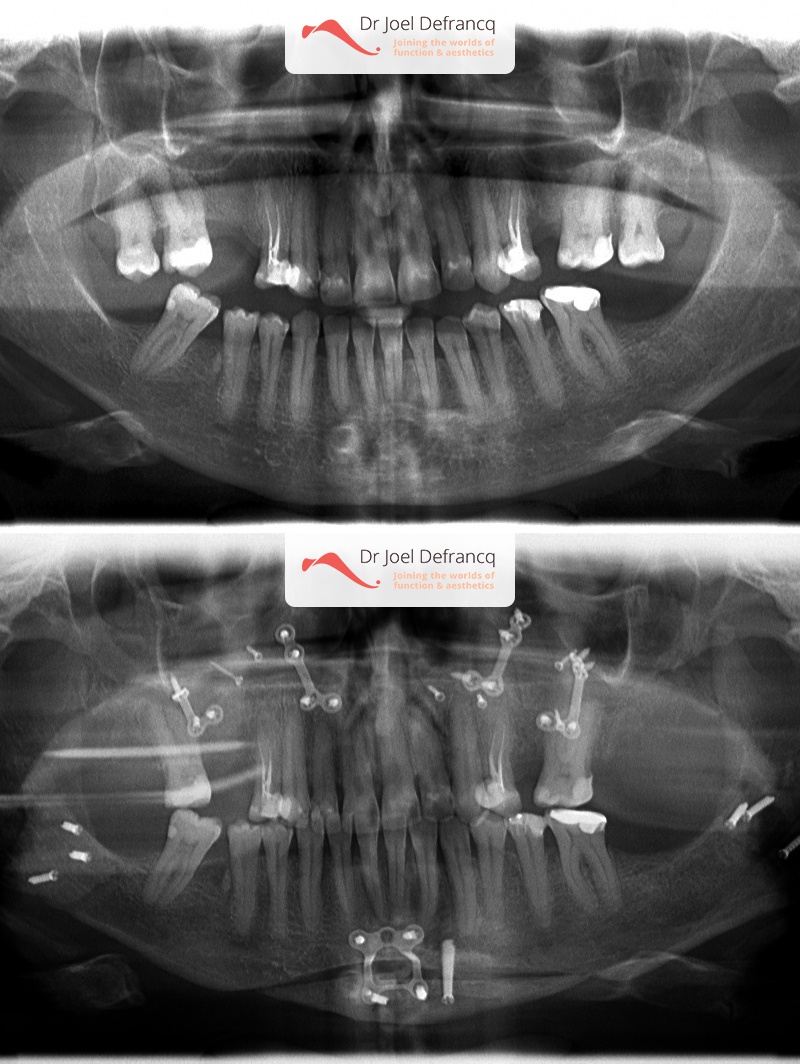

Kaakchirurgie

- Verlenging onderkaak (BSSO)

- Verlenging bovenkaak (Le Fort I)

- Rotatie bovenkaak

- Onderkaak rotatie

- Kinchirurgie